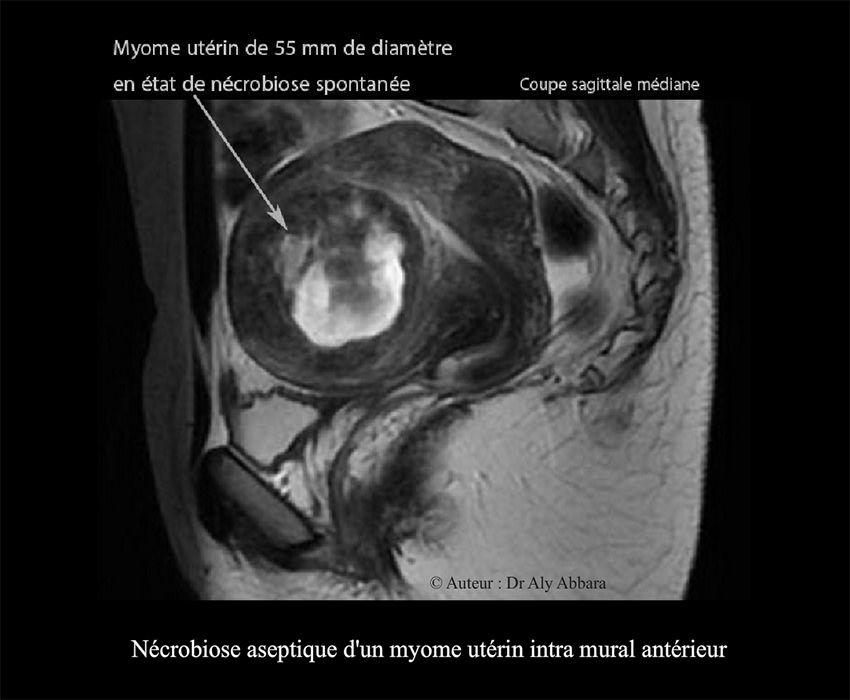

Myome utérin de 55 mm de diamètre en état de nécrobiose aseptique - Images IRM

Série d'images IRM montrant l'involution d'un myome utérin intra-mural

antérieur de 55 mm de diamètre (environ 87 cm3) remanié par une

nécrobiose aseptique.